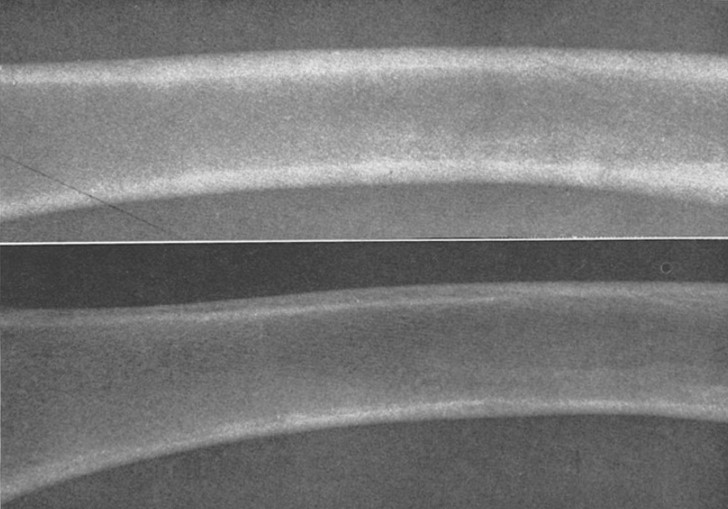

The reason for the marked decrease in C/T ratio or cortical thinning was rapid resorption in the endosteal one third of the cortex due to a sequence of events that has been described by the authors (Hanson et al., 1970). The sequence begins during the second week of treatment with the development of resorption spaces in the sub-endosteal cortex. The number and size of the resorption spaces in this area gradually increases and extends around the majority of the cortical circumference. By the end of the fourth week of treatment, the large and numerous resorption spaces begin to coalesce and undermine most of the endosteum (Fig. 4). The confluence of resorption spaces as the junction of the inner and middle one third of the cortex could be consistently appreciated on radiographs of the femur as a linear radiolucent line (Fig. 5). During the fifth and sixth weeks of treatment, the endosteal “slough” or resorption was completed, resulting in dramatic and sudden cortical thinning.

Figure 5. . Lateral X-rays of the right femur midshafts of littermates (control above and crystalline hydrocortisone-treated below) after four weeks of treatment. Note the linear radiolucent lines within the cortices. Its location corresponds to the confluence of resorption spaces seen at 4 weeks on cross-section preparation (see Fig. 4)